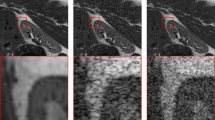

The existence of speckle noise in medical ultrasound (US) images greatly diminishes image quality and decreases diagnostic accuracy. The recent models for de-noising US images suffer from poor generalizability, a loss of texture information, and over-smoothing of the US images, especially at high noise levels. This study suggests an efficient and robust de-speckling filter for US images based on an attentional auto-encoder. This filter incorporates two distinct and efficient attention levels. The channel attention level (CAL) and large kernel attention level (KAL). These levels are integrated into the down-sampling and up-sampling steps, respectively. A skip link is added before the up-sampling stage to avoid the gradient vanishing during training. The performance of the introduced model was assessed using subjective visual evaluations and objective determination indices. The outcomes of the suggested approach on online databases achieved the minimum execution time (AET), the maximum values for structural similarity (SSIM), and peak signal-to-noise ratio (PSNR) indices over all levels of noise, exceeding other recent algorithms. For instance, at a high level of noise, the presented technique based on the breast database achieves the following mean values: 0.005, 0.81, and 23.71 dB for the AET, SSIM, and PSNR, respectively. Also, in clinical settings, the introduced model attained the highest values for the equivalent number of looks (ENL = 18.78), contrast-to-noise ratio (CNR = 5.12), and highest resolution (\(\alpha^{\sim }\) = 0.28). These findings prove that the presented architecture is more efficient and robust for rejecting noise while maintaining image details than other recent techniques.